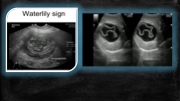

Page 37 - SONO 260 Patologías Hígado